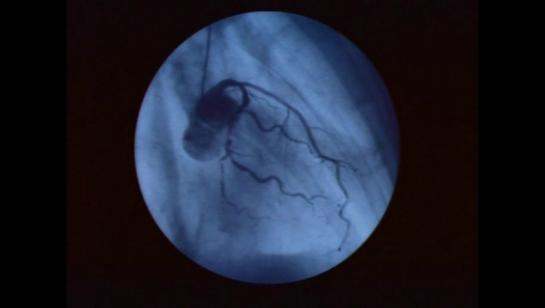

Тело человека / The Human Body (1) История жизни (1998) Кристофер Спенсер (док. сериал, BBC) by Роман Вольтов Videos 49:08 49:16 49:23 49:07 49:33 49:04 49:31 49:06